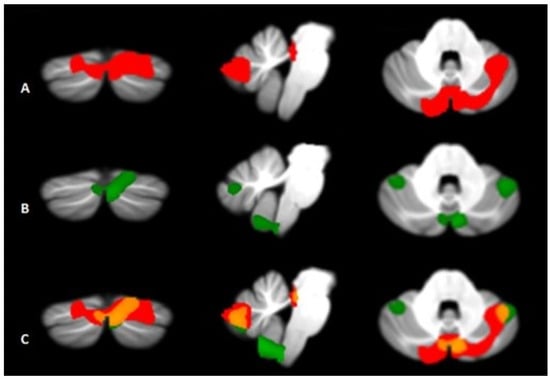

| Cerebellum | Located in the posterior cranial fossa behind the pons and medulla oblongata, separated from them by the fourth ventricle. It is divided into two hemispheres (left and right) and three lobes (anterior, posterior and flocculonodular). It is responsible for dealing with motor learning, coordination and precision of motor functions, but it also plays a role in cognitive, emotional, linguistic and visuospatial functions, thanks to connections [cortico-ponto-cerebellar (CPC) and the circuit cerebello-thalamo-cortical (CTC)] with the frontal, temporal, parietal cortices and paralimbic regions. | Functional imaging studies have highlighted a pattern of significant atrophy affecting various regions of the cerebellum (including the vermis, anterior lobe V, and posterior lobules Crus I and II), with some distinctive characteristics between subtypes: in BD-I it has been observed a reduction of the anterior and posterior cerebellar portions, more evident on the right hemisphere, while BD-II subjects show a pattern of diffuse and bilateral cerebellar atrophy. |

| Cerebellum | Reduction of the anterior and posterior cerebellar portions, with greater evidence in the right hemisphere. | Diffuse and bilateral cerebellar atrophy. |